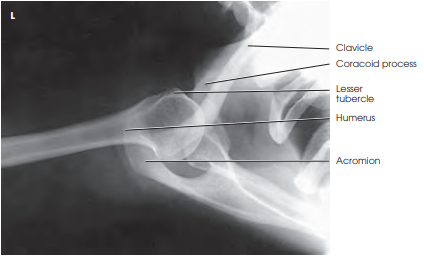

안녕하세요, 오늘은 어깨(shoulder) 촬영방법 중 하나인 superiorinferior axial 촬영법에 대해서 설명하겠습니다. 이 촬영법은 proximal humerus(상완골 근위부)와 glenoid cavity(관절와)를 관찰하기 용이합니다. ac joint(견쇄관절), coracoid process(오훼돌기), subscapularis(견갑골하근), teres minor(소원근)의 바깥부분이 보입니다. 그럼 이미지와 함께 설명 시작하겠습니다.

- Glenoidhumeral joint(상완와관절)가 잘 보여야 한다

- acromioclavicular joint(AC joint, 견쇄관절)이 잘 보여야 한다.

- lesser tubercle(소결절)의 측면상이 보여야 한다.